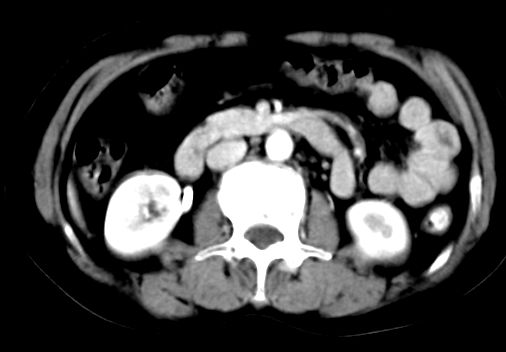

ct表现:

肝大小形态未见异常,肝内外胆管无扩张,肝s8段见一动脉期明显血管样强化结节,门脉期呈高密度,延迟期呈等密度,胆囊不大,增强扫描见胆囊及胆囊颈管壁增厚,有强化。

双肾灌注良好,代谢增快,动脉期肾盂见造影剂,左肾下极背侧见一略低密度病灶,延迟期见似不强化囊肿,双侧肾上腺未见异常。

胰腺及脾未见异常。肾门水平腹膜后见小淋巴结。腹腔未见积液征象。

诊断:

1、胆囊炎(轻度)。

2、肝s8段结节,考虑小血管瘤。

3、左肾下极低密度灶,考虑囊肿可能性大,建议随访,除外小肾癌(无强化可以基本除外)。

4、目前ct表现尚不能解释患者上腹部疼痛,建议上消造影检查,除外胃炎等疾患。